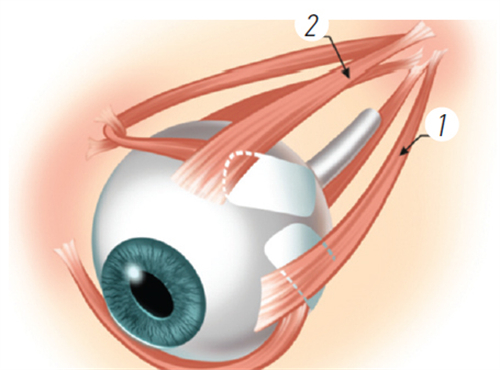

生物相容性优化:

晶体材料抗撕裂性提升,术后晶体移位风险降低,适合角膜条件复杂或瞳孔较大的患者。